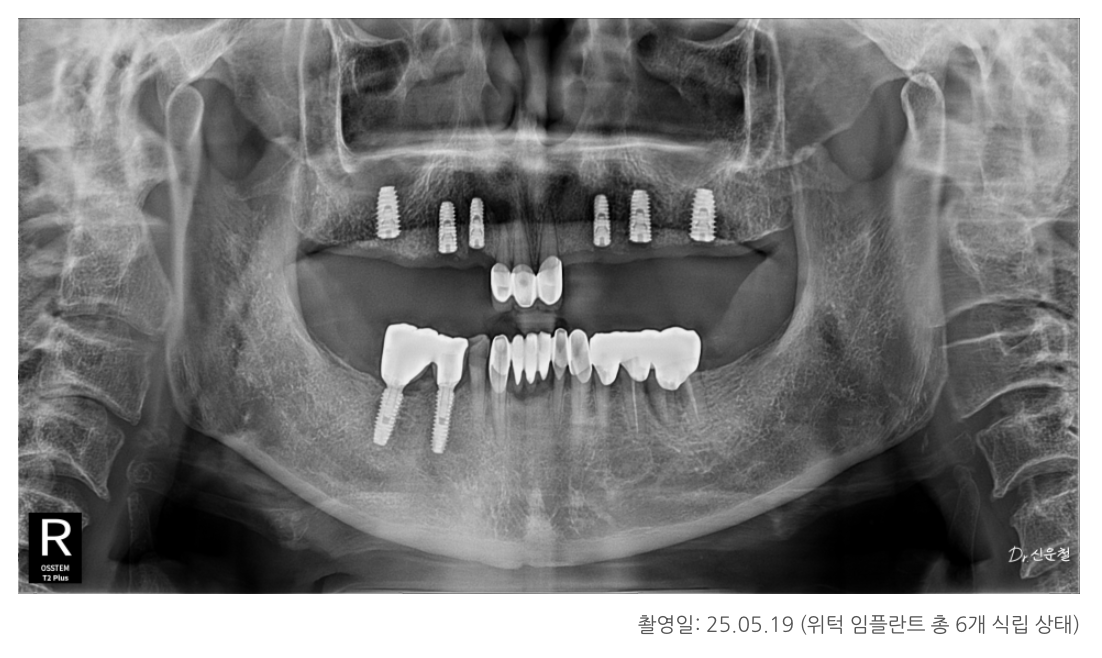

✔ 첫 내원 시 상태 (25.05.01)

앞니 세 개만 남아있는 상태

양쪽 어금니는 모두 상실

오래된 틀니 사용으로 잇몸뼈가 많이 닳아 있음

✔ 치료 방향: 총 6개의 임플란트로 기능 회복

치아 기능이 유지되는 아래턱의 범위를 기준으로

위턱 역시 좌우 6개 영역에서 맞춰 균형을 잡았습니다.